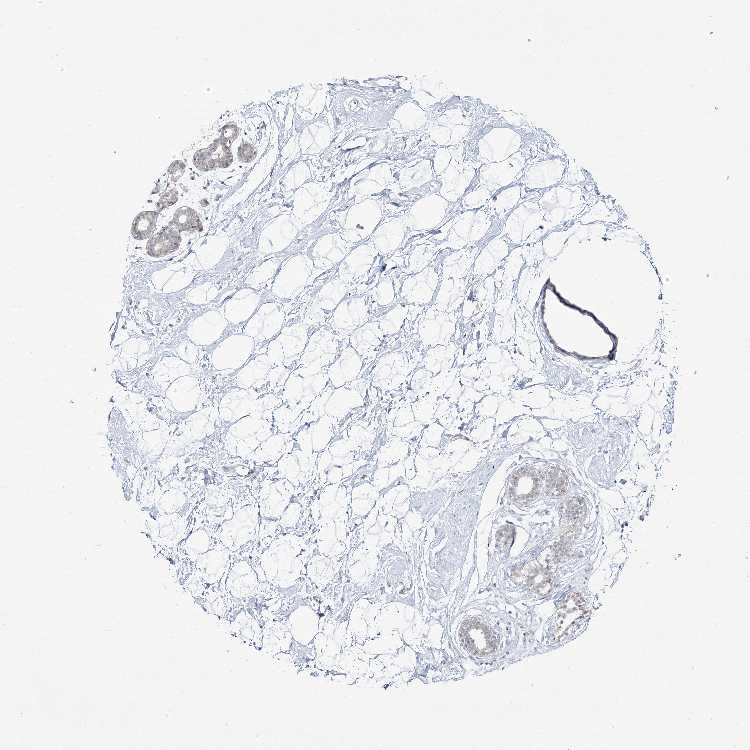

Information about each individual sample is listed below, including gender, age, a tissue section image and estimated fractions of cell types. pTPM (transcripts per million) values give a quantification of the gene abundance which is comparable between different genes and samples.

Female, age 80

Breast sample 390 pTPM: 4.4

Cell types%

Glandular cells: 5 Adipocytes: 15 Other cell types: 80

Female, age 47

Breast sample 405 pTPM: 3.9

Glandular cells: 5 Adipocytes: 5 Other cell types: 90

Female, age 38

Breast sample 410 pTPM: 8.6

Glandular cells: 40 Adipocytes: 5 Other cell types: 55